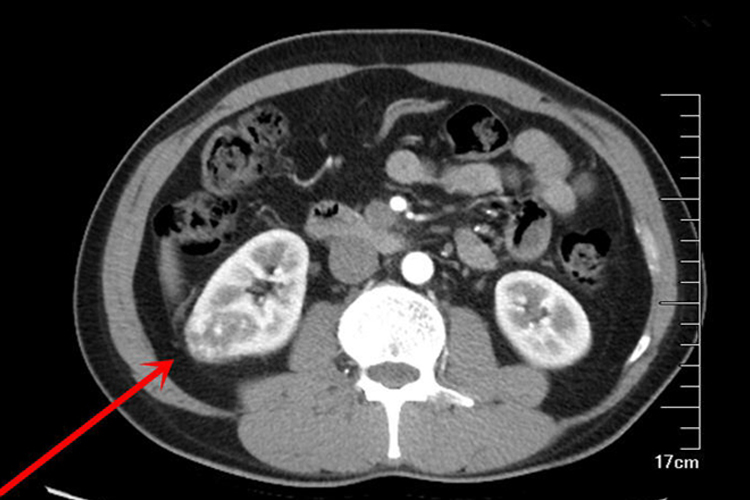

恶性肾肿瘤常见于肾癌,患者可出现发热、贫血、红细胞增多症、高血压、肝功能异常、高血钙、血沉增快、精索静脉曲张等。晚期可出现消瘦、贫血、虚弱等恶病质改变。CT检查表现为肾实质内圆形,类圆形或分叶状肿块,平扫时密度不均匀。CT值为低于正常肾组织的正值。